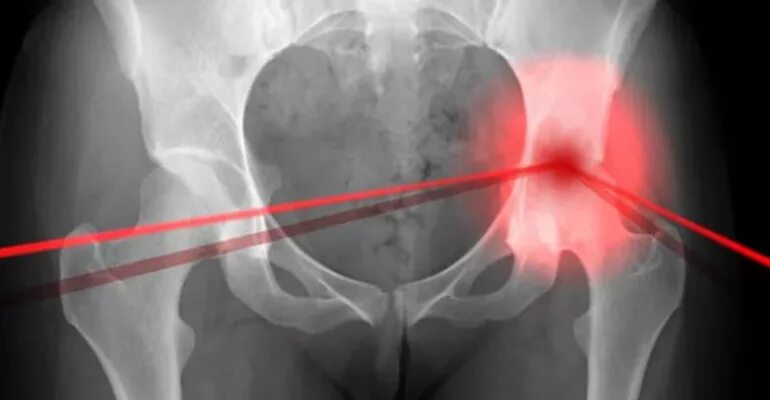

Артрит тазобедренного сустава симптомы